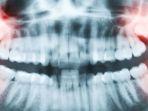

Gigi bungsu yang impaksi dapat menimbulkan rasa sakit, pembengkakan, dan bahkan infeksi jika tidak ditangai dengan baik.

Impaksi gigi bungsu adalah permasalahan gigi yang sering dialami oleh orang dewasa karena gigi tidak tumbuh dengan sempurna.

Ada beberapa metode penanganan yang dapat dilakukan untuk menangani impaksi pada gigi bungsu.